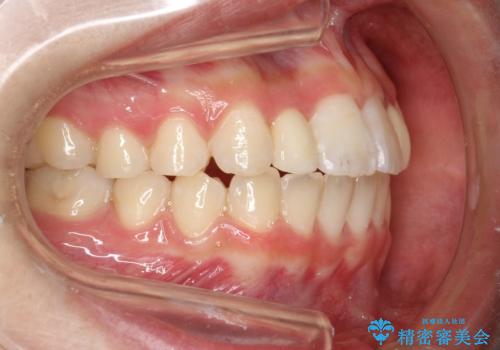

上あごの2番目の歯は矮小歯といって、生まれつき小さい歯となる事がよくあります。

このような場合、矯正によりスペースを集め、本来あるべき形態にセラミックで修正することもできます。